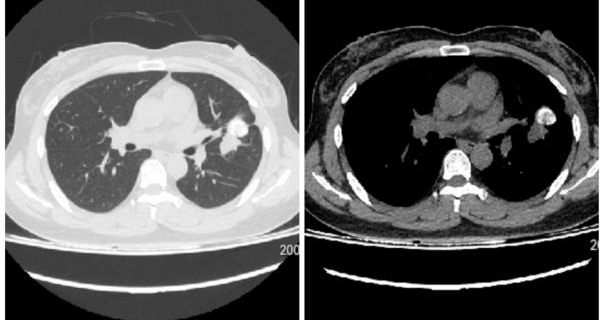

患者张某,今年52岁,一周前在当地医院进行常规健康体检时,胸部CT检查提示肺部存在阴影,进一步检查后发现肺部有2个结节,其中1个结节已出现钙化迹象,另1个直径约8毫米的结节未发生钙化,且形态不规则,存在恶性病变的潜在风险。尽管张某目前没有出现明显的咳嗽、胸闷、咯血、胸痛等不适症状,但得知肺部结节可能存在恶性风险后,他内心十分焦虑,日夜忧心忡忡,生怕延误病情治疗。在家人的陪同下,张某多方打听后,特意来到延安市人民医院呼吸与危重症医学科一病区就诊,寻求专业的诊疗帮助。

术前,医疗团队周密筹备,为患者量身制定个性化手术方案,并通过肺部薄层CT三维重建技术,精准规划手术操作路径;管床医师贺朴住院医师与患者及家属充分沟通,详细讲解手术细节、潜在风险及对应处置措施,耐心安抚其焦虑情绪,做好术前沟通与心理疏导。术中,在手术麻醉科的紧密配合下,贾莉副主任医师带领团队规范操作,借助Lungpro导航系统实现病灶精准定位,顺利完成经肺实质结节抵达术,成功获取足量病变组织,手术全程顺利。患者术中无明显不适,为后续诊断与治疗提供了关键病理依据,患者及家属对诊疗效果表示高度满意。后续病理检查结果提示:患者左肺下舌段肺组织存在坏死表现,局部可见疑似结核相关特征细胞,特殊染色检测发现少量结核杆菌,临床整体倾向于结核性炎症。